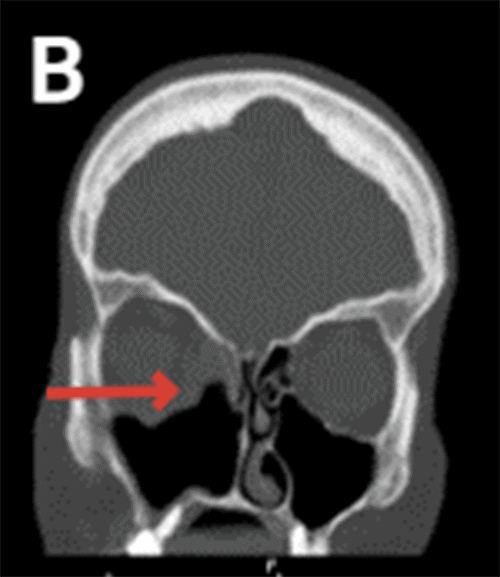

Non-contrast head CT reported the absence of the medial wall of the right maxillary sinus as well as the right inferior nasal turbinate with moderate mucosal thickening within the right frontal, bilateral ethmoid, right sphenoid, and maxillary sinuses indicating chronic sinusitis (Figure 1).

Figure 1. CT Imaging Demonstrating Patient's Extensive Bony Destruction. Published with Permission

C) Arrow pointing at ill-defined inferior rectus muscle

Patients with chronic invasive sinusitis with mucormycosis present with non-specific symptoms, including facial pain, facial pressure, headache, mucoid nasal discharge, fevers, nasal congestion, periorbital edema, proptosis, blindness, and cacosmia with the most frequently reported of these being unilateral facial pain.1 Of note, our patient reported several symptoms, including nasal congestion, facial pressure, visual changes, eye drooping, and sinus drainage, for months before presenting to our office. Diagnostic workup includes head CT, MRI, nasal endoscopy, and surgical intervention to retrieve cultures and tissue biopsies for pathologic confirmation. Imaging modalities can reveal the destruction of nasal turbinates, bony erosions, and hyperattenuating allergic mucin. Our patient's diagnostic imaging revealed extensive underlying bony destruction despite having minimal dysmorphic facial features before surgical intervention.